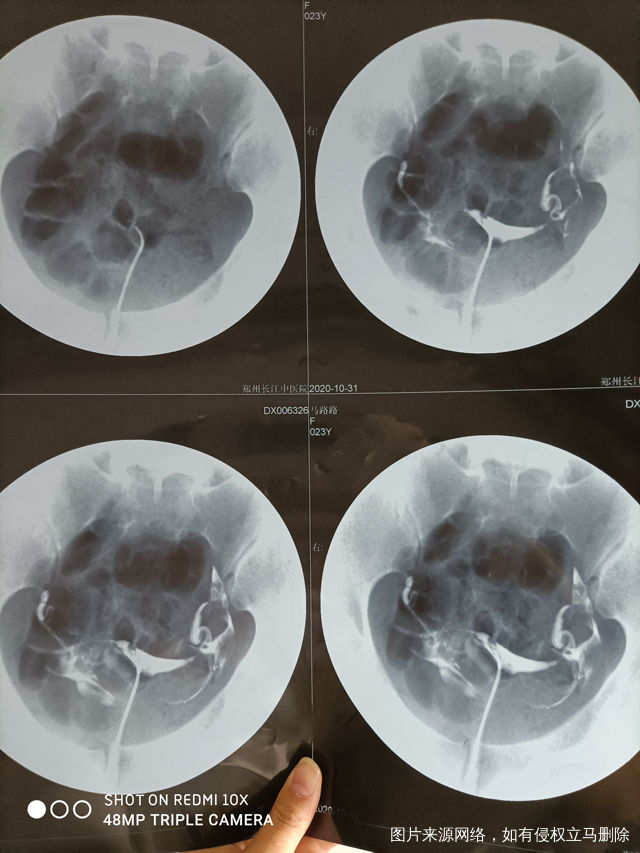

做完输卵管造影第六天了小腹还是感觉沉甸甸的如

可以热敷腹部,如果有发热,腹痛加剧,白带量多,有异味,随时就医